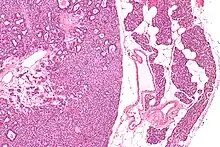

| Micrograph of a parathyroid adenoma (left) and normal parathyroid gland (right). H&E stain. | |